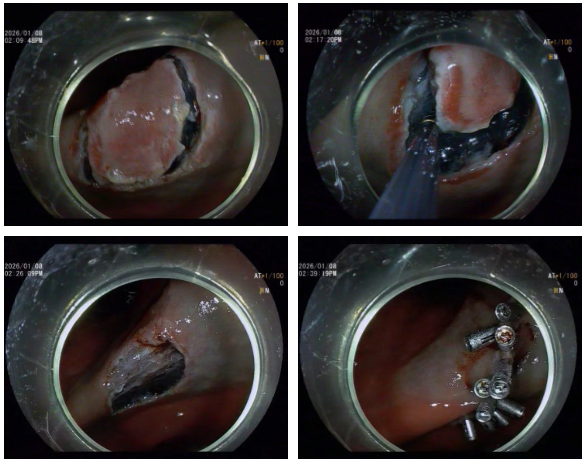

经验丰富,常规检查揪出隐匿病灶

消化内科杨贵祥主治医师为其实施内镜检查中敏锐发现其胃窦表面粗糙不平坦伴有发红及糜烂,凭借多年临床经验,杨医生结合胃镜下特殊光染色,初步判断该处组织可能为恶性病变的潜在风险,立即取病理两块进行送检。同时密切与患者保持联系,病理结果回示:胃窦粘膜慢性活动性炎,伴面膜上皮和腺体高级别上皮内瘤变,局部疑小灶间质浸润。针对沈大叔的病情,消化内科吴勇主任带领团队进行充分术前论证,决定采用内镜黏膜下剥离术(ESD)进行治疗。手术由吴勇主任主刀,术中凭借精湛技巧仔细分离病灶与正常组织,最终成功完成剥离,整个手术过程未出现出血情况。

什么是“ESD”? ESD的全称是内镜黏膜下剥离术,即医生通过患者口腔或肛门,将带有高清摄像头和特殊器械的内镜伸入消化道,在病变组织下方注射药物使其抬起,再用专用刀器将病变完整剥离并取出,全程无需开腹,仅在消化道黏膜表面操作。